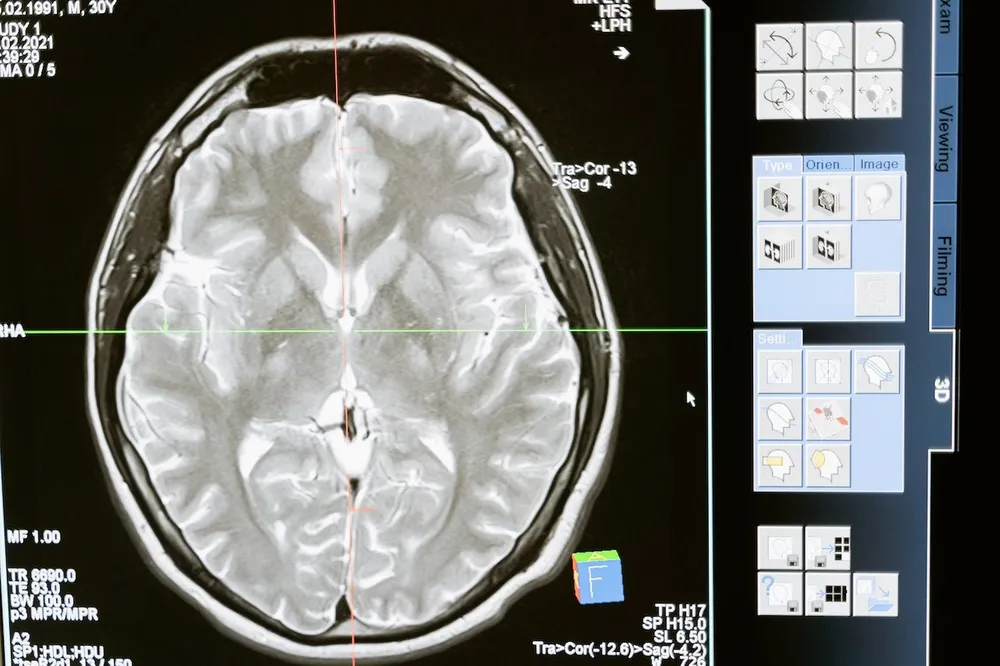

Hvis man oplever ovenstående symptomer, bør man gå til sin egen læge, som så kan henvise til yderligere undersøgelse hos neurolog eller neurokirurg. Ved mistanke om hjernetumor laves en CT-eller MR-scanning af hjernen, evt. med røntgenkontrast.